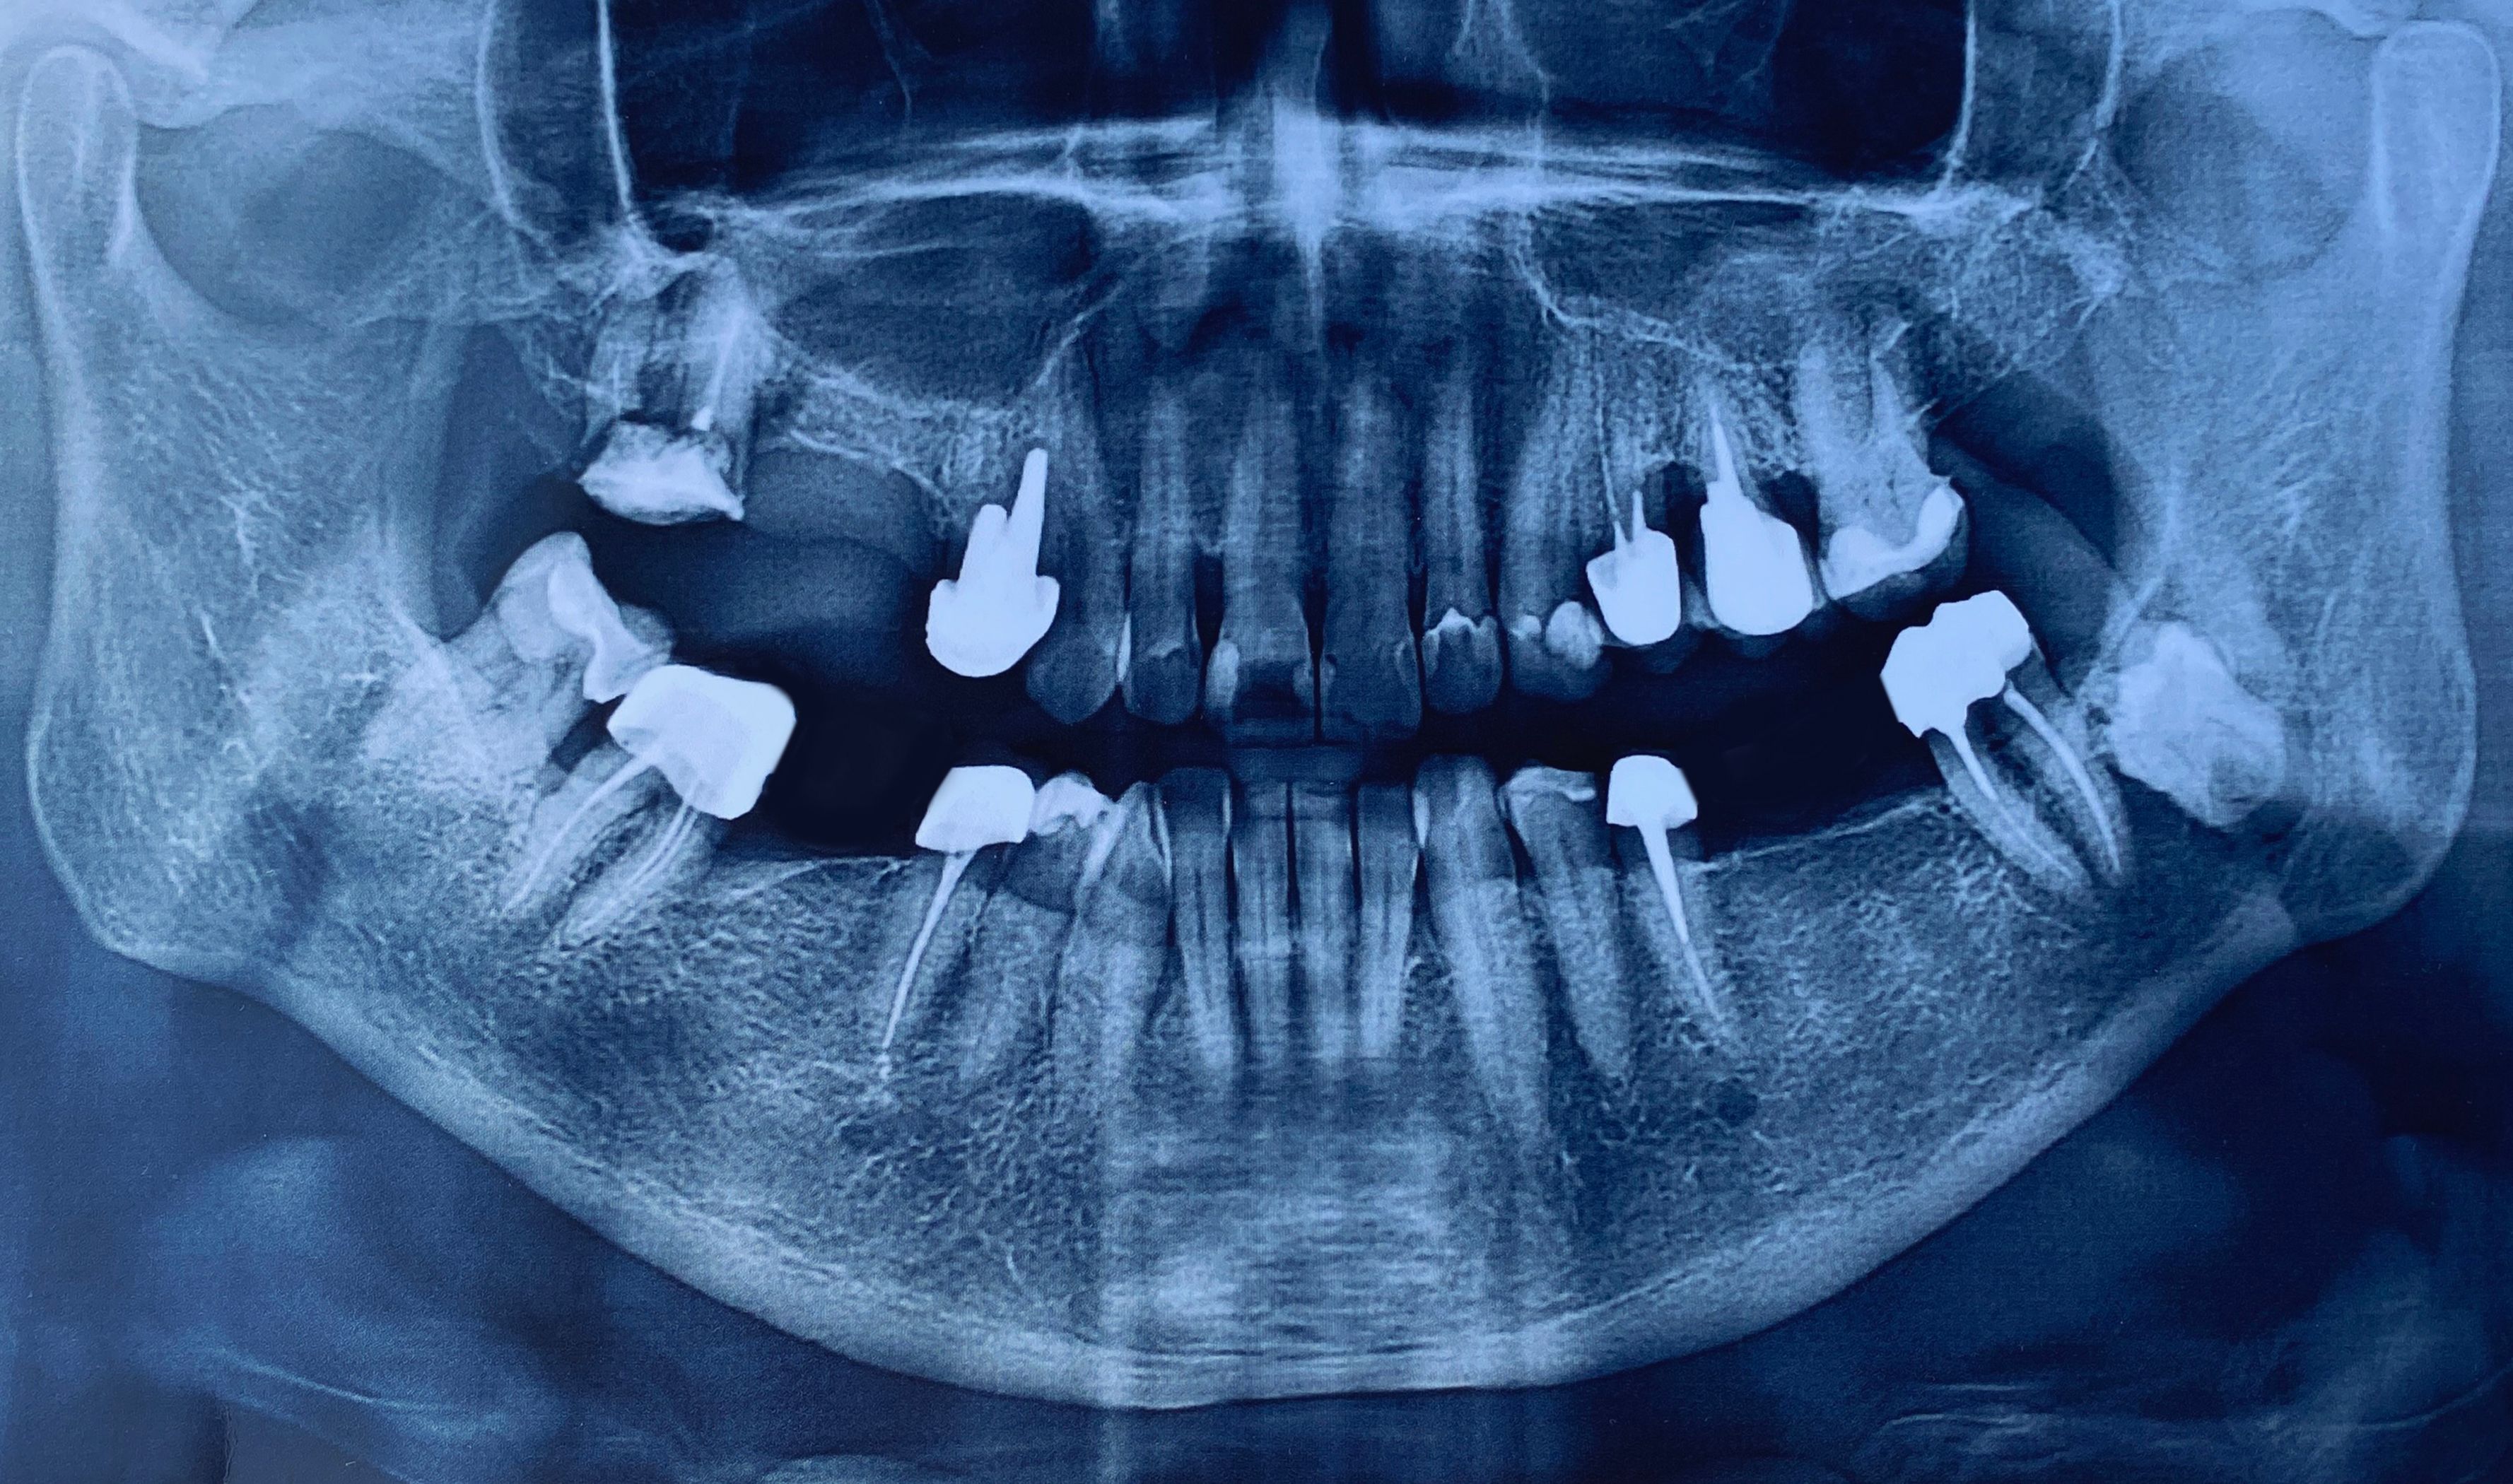

A root canal is necessary when the pulp inside a tooth becomes infected or inflamed. This can be due to deep decay, repeated dental procedures on the tooth, or a crack or chip in the tooth. Sometimes, even trauma to a tooth may cause pulp damage even if the tooth has no visible chips or cracks.

Some people believe that extracting a tooth is a better solution than undergoing a root canal. However, preserving your natural teeth should always be the priority. A root canal can save your tooth and help maintain your natural smile, allowing you to continue eating the foods you love with ease. Extraction, on the other hand, can lead to other dental issues and often requires additional procedures like implants or bridges.